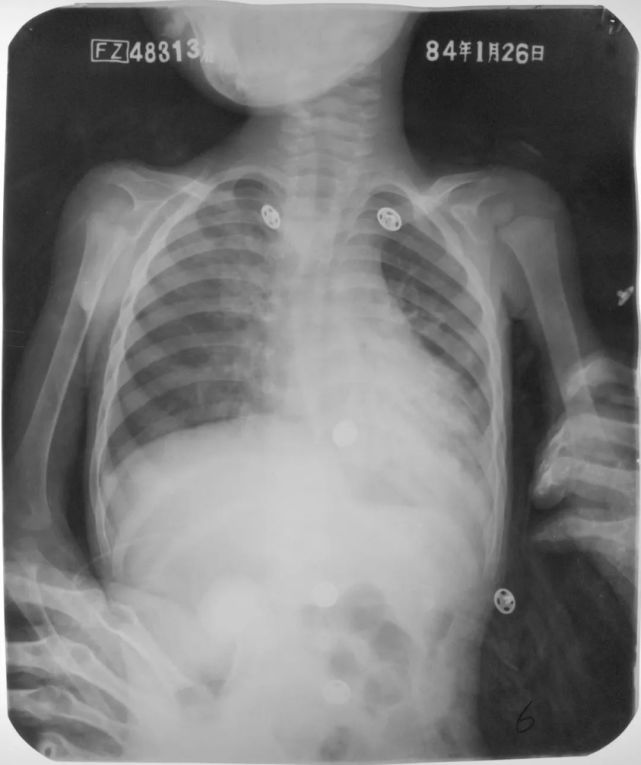

急性粟粒型肺结核(三均匀)

图片

胸部正位片:两肺弥漫性分布大小不等的、分布均匀的粟粒状密度增高影,边缘模糊